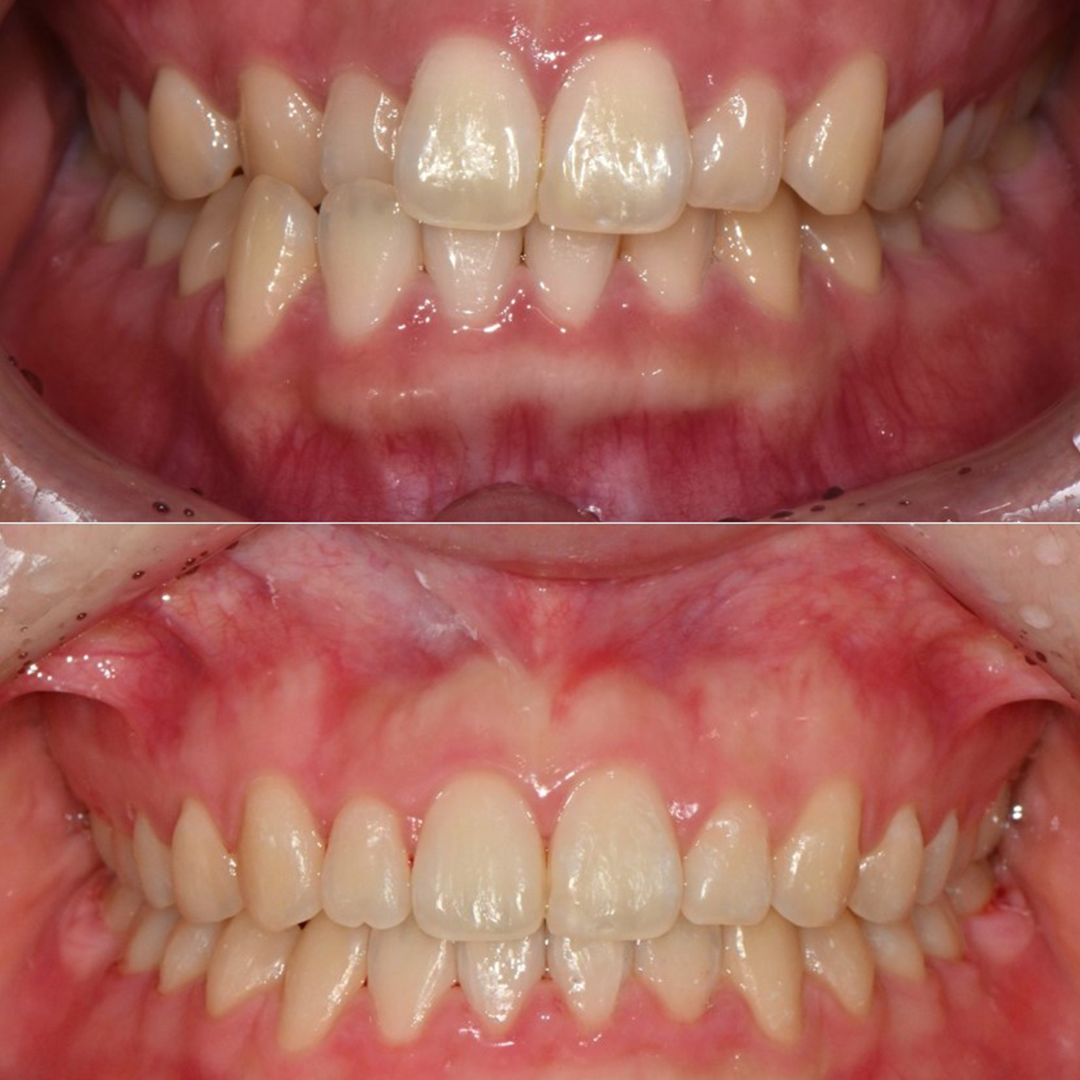

평균 악당 30분의 빠른 식립시간, 치료 케이스 다수 보유

전체 임플란트

상·하악 전체 치아를 대체하는 임플란트로 최소한의 식립을 통해

자연치아와 비슷한 기능을 수행할 수 있도록 합니다.